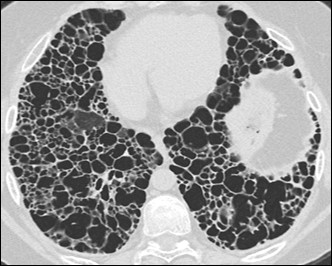

UIP: Example

UIP shows:3,6

- Subpleural and basal predominant distribution

- Honeycombing

- Traction bronchiectasis

The distribution of UIP is characteristically basal and peripheral, though often patchy.1,3,5,6

Image courtesy of and used with permission from Robert Suh, MD.

Honeycombing is critical for an HRCT diagnosis of UIP without surgical biopsy.1,3,5-7

In cases of UIP, ground-glass opacities (GGO) may be present but should be less extensive than the reticulation.1,3,6 Mediastinal lymphadenopathy may be present.3